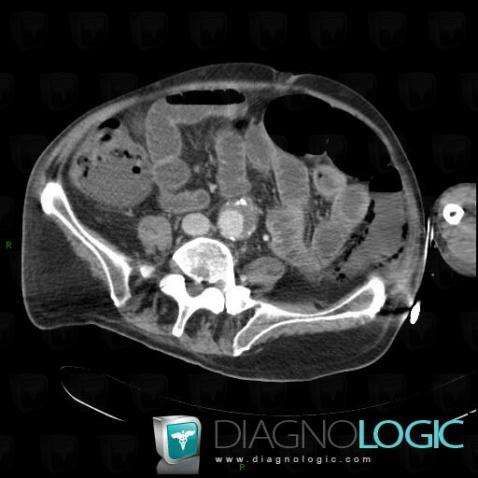

Ischemic colitis, Colon, CT

Here is the specific information in the key image above:

- Diagnosis Ischemic colitis, Location(s) Colon, with gamuts

- Diagnosis Ischemic colitis, Location(s) Colon, with gamuts Thickening of colon wall